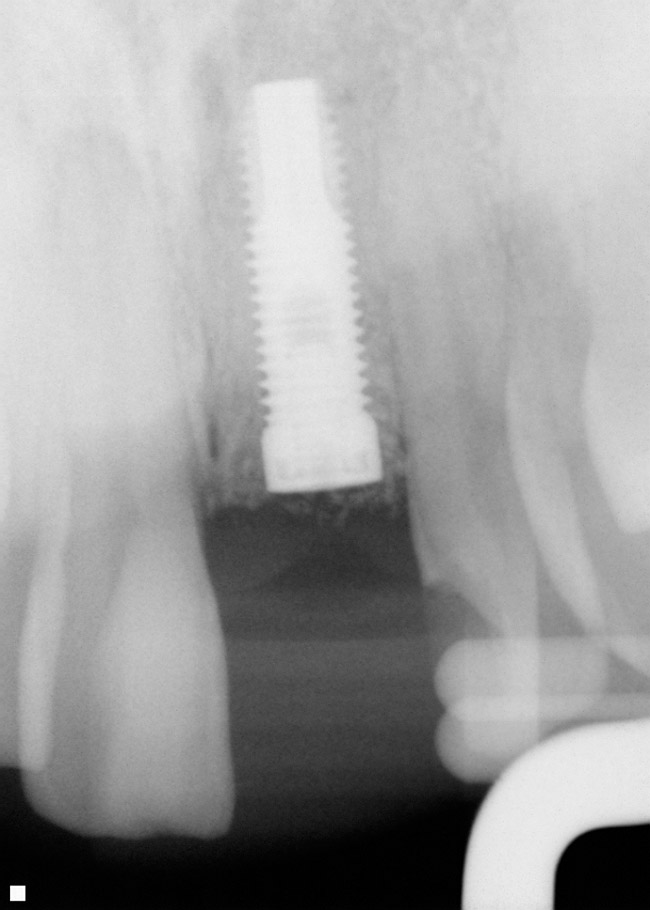

Alveolele postextracţionale au fost lăsate să se vindece pentru o perioadă medie de 6 luni. După vindecare, s-au inserat în total 109 implante. Nu s-au înregistrat eşecuri de grefare şi implantele au fost aplicate în toate cele 109 locaţii grefate. Un total de 58 de implante au fost introduse cu reflecţia lamboului, iar 51 cu tehnica fără lambou/prin perforare. S-au folosit implante endoosoase într-o singură etapă şi în două etape, reprezentând diferite forme de implante. Diametrele implantelor au variat de la 3,3mm până la 5mm, cu lungimea implantelor variind între 10-15mm, în funcţie de consideraţiile restauratoare şi localizările în cadrul alveolelor. Toate implantele inserate aveau design cu suprafaţă rugoasă. Din cele 109 implante inserate, 67 au fost aplicate la maxilar şi 42 la mandibulă. Un total de 33 de implante au fost inserate la fumători (11 pacienţi) şi 76 de implante la nefumători (58 pacienţi).

Din cele 109 implante inserate la cei 69 pacienţi în cursul unei perioade de 4 ani, nu s-a înregistrat niciun eşec implantologic după inserţia dispozitivelor fixe şi restaurarea protetică ulterioară. La descoperirea implantelor, nu erau semne de mobilitate a acestora, şi toate implantele inserate au fost restaurate. În momentul prelucrării datelor, toate implantele au rămas complet încărcate şi în funcţiune, rezultând o rată de supravieţuire de 100% (tabelul 1). Ca şi grup, implantele erau funcţionale şi încărcate de o perioadă medie de 2 ani, variind între 6-65 luni. Indiferent de tipul implantului, localizarea în alveolă, statusul de fumător, 100% din implante sunt în funcţiune şi actualmente (tabelul 1 şi fig. 1-9).